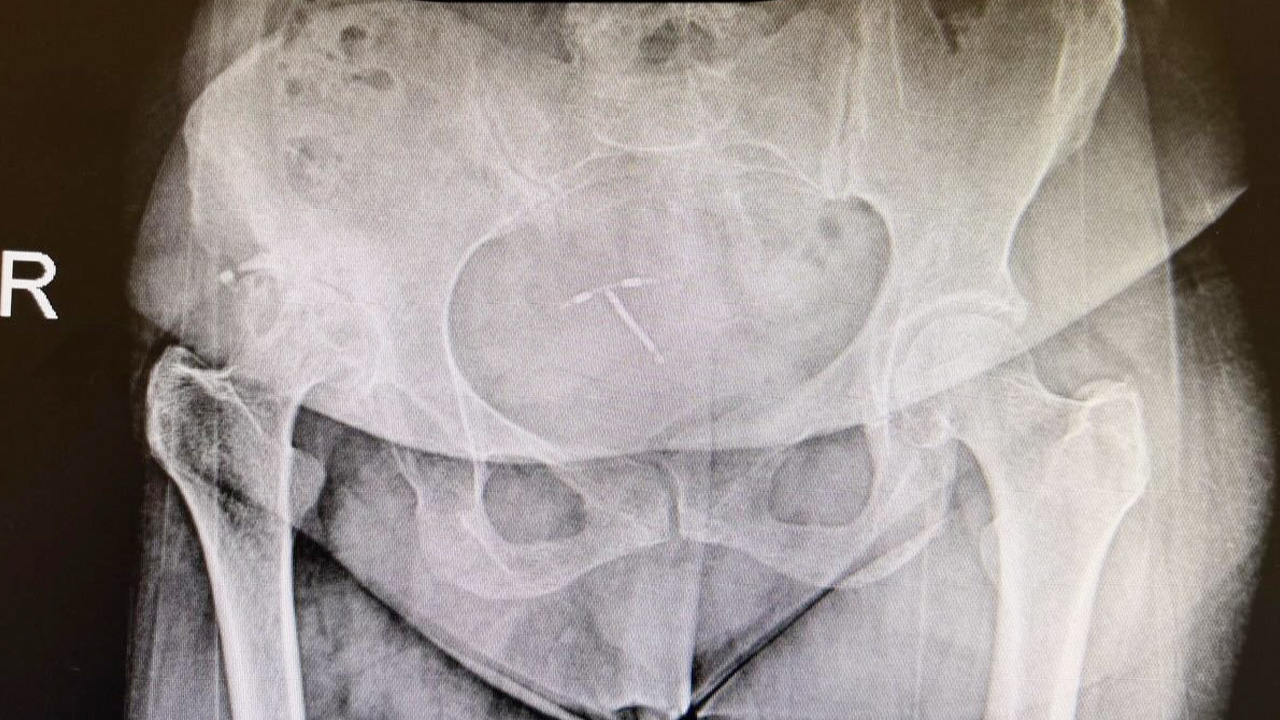

Sarıkaya Devlet Hastanesi Ortopedi ve Travmatoloji Uzmanı Op. Dr. Mevlüt Kutay Akkaya, doğuştan kalça çıkığına bağlı bacak kısalığı ve yürüme bozukluğu bulunan 50 yaşındaki kadın hastaya ileri düzey cerrahi müdahale uyguladı.

Literatürde yüksek uzmanlık gerektiren bir yöntem tercih edilerek, femur kısaltma işlemi yapılmadan anatomik total kalça protezi ameliyatı gerçekleştirildi. Operasyon sürecinde protezin anatomik yerleşimi ve bacak boylarının eşitlenmesi büyük bir titizlikle planlandı.

Başarıyla tamamlanan ameliyatın ardından hasta, yalnızca bir gün sonra desteksiz ve aksamadan yürümeye başladı. Kısa sürede sağlanan bu hızlı iyileşme süreci, uygulanan cerrahi tekniğin doğruluğunu ve hekimlik başarısını ortaya koydu.